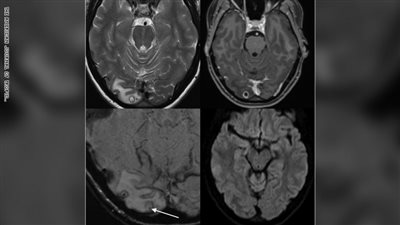

اكتشف الأطباء في استراليا وجود يرقات ديدان في دماغ أمراة، تبلغ من العمر حوالي 25 عاماً، وقد أحتلت الدودة الشريطية مكاناً في دماغ المرأة .